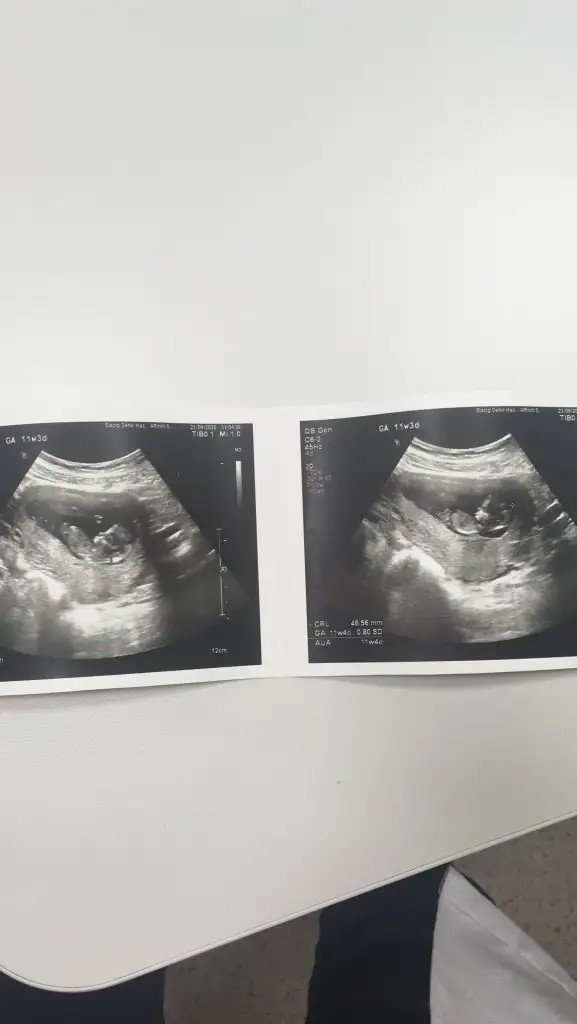

Erkek mi dediBana da yorum yaparmısınız lütfen. Bugün geldim doktordan. Cinsiyeti söyledi ama kesin olarak bi ay sonra dedi

Çünkü kordonu pipi sanma ihtimalleri varKız dedi ama kesin sonucu bir sonraki randevuda söylicem dedi. Ama emindir bence.14+3 sonuçta. Daha nezaman kesinleşir ki. Değişme ihtimali varmıdır ?

10+3 11 satılıyor diye attim ama garanti olsun diye sana 12+5 de felan gelcemBir tomurcuk var sanki erkek olabilir yinede USG istiyorum net değil birde 11 hafta değil sanirim

12 haftalığa göre çok net göstermiş masallahUSG 12.3 şimdi 17 haftalik